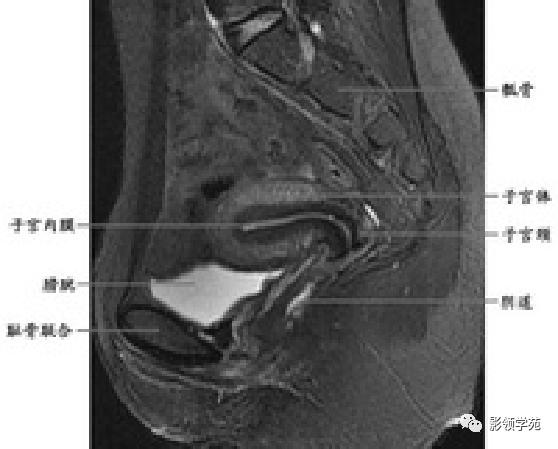

子宫

- 子宫位于骨盆的中央;长约7~8厘米,宽约4~5厘米,厚约2~3厘米,呈倒置的梨形

- 前面借膀胱阴道隔与膀胱底相邻;后面借直肠子宫陷凹及直肠阴道隔与直肠相邻

- 分为子宫底、子宫体和子宫颈三部分

T1WI:呈均匀低信号,周围为高信号脂肪

T2WI : 宫体三层:

中心高信号---子宫内膜和分泌物;

中间低信号带---子宫肌内层,亦称结合带;

周围呈中等信号---子宫肌外层

T2WI图像可显示子宫体三层

结构

- 子宫内膜-高信号

- 结合带-低信号

- 子宫肌层-中等信号